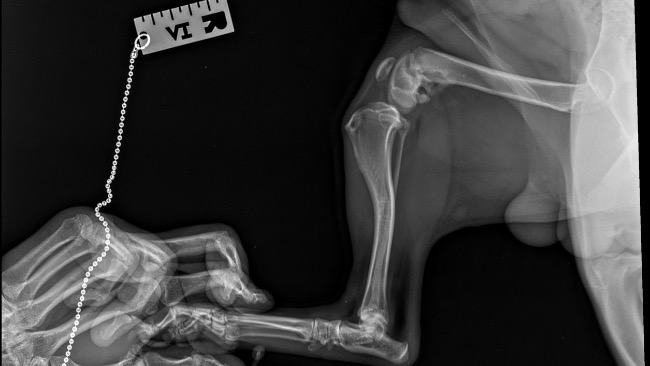

Mam na imię Julia i mam 9 lat. Kilka dni temu mój tata znalazł porzuconego pieska i postanowiliśmy go przygarnąć. Jak udało nam się ustalić od ludzi mieszkających w pobliżu miejsca znalezienia Aksela, (tak dostał na imię) pies błąkał sie tam od 2 miesiecy, wracał codziennie w to samo miejsce jakby czekal na swojego właściciela. Jakiś czas temu potracił go jeszcze samochód. Weterynarz ocenił wiek Aksela na 8-9 miesięcy. Niestety okazało się, że ma złamaną tylną prawą nogę. Dostaje leki znieczulające i dzięki temu tak bardzo nie kuleje. Konieczna jest jednak operacja aby beztrosko mógł cieszyć się życiem. Nie jest to jednak standardowe złamanie stąd też wysoka cena operacji. Weterynarz uprzedzał nas tez o możliwych komplikacjach. Jednak operacja jest potrzebna gdyż pozostawienie nogi w aktualnym stanie w przyszłości będzie rzutowało na jego zdrowie. Jest to dla mnie bardzo ważne. Proszę pomóżcie mi zebrać 2000 zł na operację łapy mojego pieska.